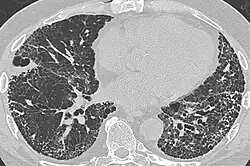

CT scan of a patient with UIP. There is interstitial thickening, architectural distortion, honeycombing and bronchiectasis.

Radiologically, the main feature required for a confident diagnosis of UIP is honeycomb change in the periphery and the lower portions (bases) of the lungs.[3]

On high-resolution computed tomography (HRCT), the following categories, depending on imaging findings, have been recommended by a collaborative effort by the American Thoracic Society, European Respiratory Society, Japanese Respiratory Society, and the Latin American Thoracic Society:[4]

• UIP pattern:[4]

• Honeycombing, with or without peripheral traction bronchiectasis; or bronchiolectasis (dilatation of the terminal bronchioles)[5]

• Predominantly subpleural and basal

• Often heterogenous distribution, being occasionally diffuse, and may be asymmetrical

There may be superimposed CT features such as mild ground-glass opacity, reticular pattern and pulmonary ossification.